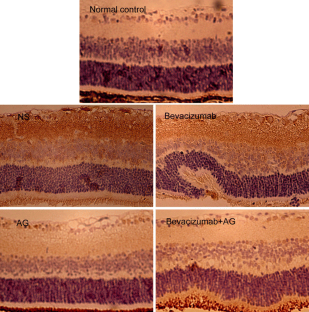

Compared with NS-treated eyes, retinal VEGF and iNOS mRNA expressions were significantly reduced in AG- and bevacizumab+AG-treated eyes; whereas in bevacizumab-treated eyes, retinal VEGF mRNA expression increased and iNOS mRNA expression remained unchanged. The above changes were confirmed by immunohistochemical study. The generalized decrease in both VEGF and iNOS distributions in mice retina treated with AG or bevacizumab+AG was demonstrated by immunohistochemistry. Retinal NV was significantly reduced in all three groups treated with bevacizumab, AG or bevacizumab+AG, when compared with NS-treated eyes.